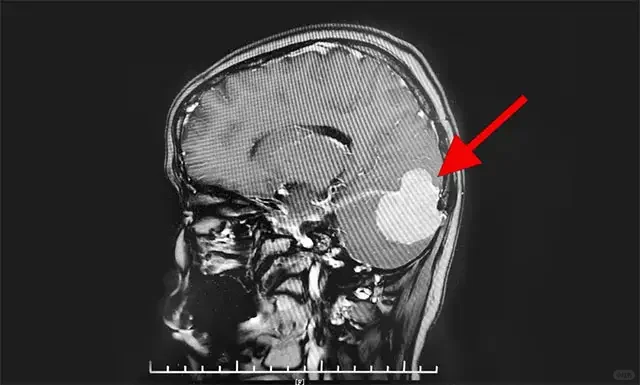

2️⃣骨瘤

枕骨骨瘤是颅骨骨瘤的一种,一般会表现为枕骨突出,骨瘤呈缓慢生长的无痛肿块,可在枕骨头皮下扪及,其表面光滑,无压痛、不活动,如骨瘤体积增大,压迫神经,可伴随头晕、头痛、恶心、四肢麻木等症状。

2️⃣骨瘤

颅骨骨瘤是起源于骨密质和骨松质的良性肿瘤,生长在枕骨部位,病因和发病机制尚不明确,可能是由于组织细胞异常增生,导致枕骨突出的症状。

2️⃣骨瘤:骨瘤体积小者建议密切观察,如果骨瘤体积增大,出现明显压迫,并影响外观,需要行手术切除治疗。